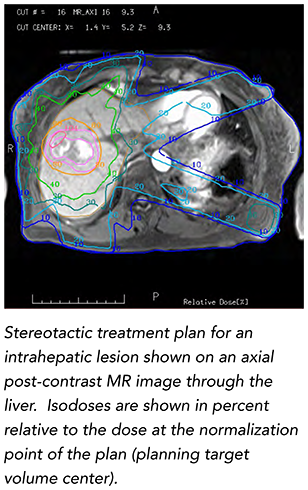

In recent years, we’ve made great strides in optimizing the integration of MRI in Radiation Oncology. In fact, it’s not difficult to imagine a day when MRI becomes the primary method of therapy planning simulation and image guidance for a variety of treatment indications. While CT has long been the preferred modality for radiation therapy due to its geometric reliability and easy conversion to representation of electron density in support of dose calculations, MRI has been a useful adjunct because of its improved ability to discern soft tissue anatomy.MRI is now recommended for volumetric treatment planning in cervical cancer brachytherapy,1 and CT/MRI fusion is now standard practice in radiation therapy. The application of MRI in radiation oncology is not without its challenges, however. In this inaugural issue of the AAPM Research Spotlight, James Balter offers his perspectives on the growing use of MRI for therapy planning, guidance, and assessment treatment response as well as major areas of research and new opportunities provided by AAPM for its members to improve understanding and utilization of MRI in radiation oncology.

Balter explains that larger magnet bores and improved field homogeneity have supported the potential role of MRI in treatment simulation. Numerous studies indicate that quantitative measurements of perfusion, diffusion, and spectroscopy from MR systems may serve as a biomarker for supporting personalized therapy, supporting assessment of treatment and, if necessary, adaptation mid-therapy course. Various efforts are underway to support MRI in place of CT capabilities by providing a synthetic model of the patient that sufficiently represents radiation attenuation and geometric configuration.2 Vendors are making MRI-compatible immobilization as well as laser-based positioning systems. They are optimizing imaging sequences for the needs of radiation oncology and improving the integration of imaging coils with immobilization systems. Most adaptations to MRI scanners to accommodate radiation therapy simulation primarily require software and inexpensive hardware modifications. As most radiation oncology clinics have access to MRI outside of the department, enhancement of such systems is a cost-effective means of supporting MRI-based simulation for smaller departments.